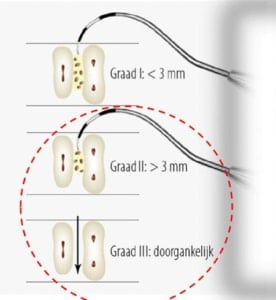

Gebistelementen met furcatie problemen hebben over het algemeen een slechtere prognose. Daarom werd in de praktijk ook het lange termijn resultaat van elementen met furcatiegraad II en III onderzocht. De resultaten laten zien dat na gemiddeld 13-jaar 67% van de elementen behouden konden blijven. Onder de molaren met furcatie II bleef 31,3% stabiel en 32,8% toonde zelf verbetering. Onder de molaren met furcatie III vertoonde slecht 18,9% stabiliteit en maar 8,9% verbeterde. Furcatie III bleek ook geassocieerd met een hoge kans op gebitsverlies. Als kantekening is het belamgrijk om te realiseren dat furcatie niet uitsluitend een parodontale oorzaak kan hebben. Ook endodontische oorzaken, zoals aanwezige laterale kanalen kunnen zorgen voor botafbraak in het furcatiegebied. Dit werd niet apart geëvalueerd.

Gebistelementen met furcatie problemen hebben over het algemeen een slechtere prognose. Daarom werd in de praktijk ook het lange termijn resultaat van elementen met furcatiegraad II en III onderzocht. De resultaten laten zien dat na gemiddeld 13-jaar 67% van de elementen behouden konden blijven. Onder de molaren met furcatie II bleef 31,3% stabiel en 32,8% toonde zelf verbetering. Onder de molaren met furcatie III vertoonde slecht 18,9% stabiliteit en maar 8,9% verbeterde. Furcatie III bleek ook geassocieerd met een hoge kans op gebitsverlies. Als kantekening is het belamgrijk om te realiseren dat furcatie niet uitsluitend een parodontale oorzaak kan hebben. Ook endodontische oorzaken, zoals aanwezige laterale kanalen kunnen zorgen voor botafbraak in het furcatiegebied. Dit werd niet apart geëvalueerd.